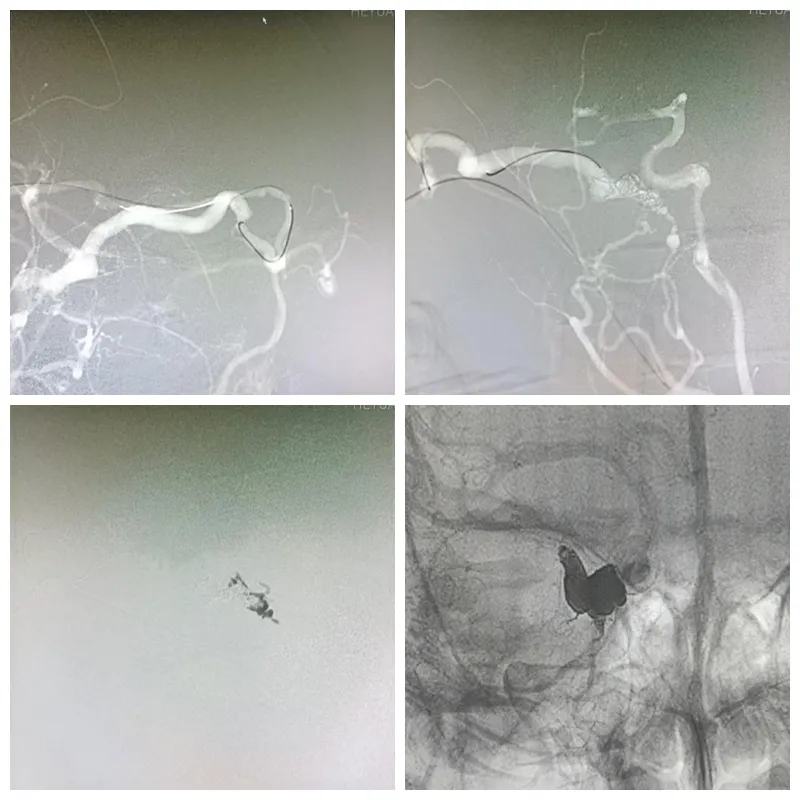

▲多角度造影,确认静脉通路

▲经颈外静脉通路微导管到达瘘口,弹簧圈联合Onyx胶成功栓塞

手术在气管插管全麻下进行,DSA造影下寻找到经右颈外静脉-眼上静脉通路,在微导丝辅助下将Marathon漂浮导管“翻山越岭”超选送至瘘口处,填入弹簧圈令静脉血缓慢、并起到“钢筋”固定作用,然后经同一根导管注入Onyx胶,胶水缓慢往瘘口及附近引流静脉弥散,最后多角度造影,提示瘘口已被“钢筋混泥土”栓塞。